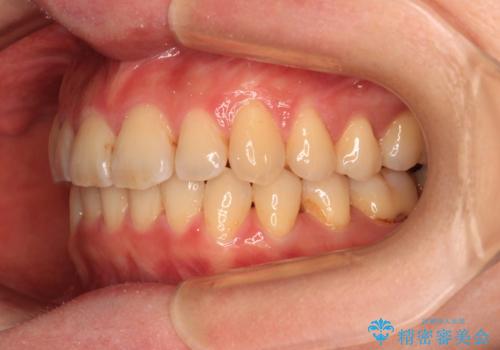

- 上下前歯のデコボコを気にして来院された患者様です。

叢生は軽度で、ワイヤー矯正でもマウスピース矯正でも対応可能な歯列でした。

僅か1年間できれいに歯列を整えることができ、患者様には大変満足していただきました。